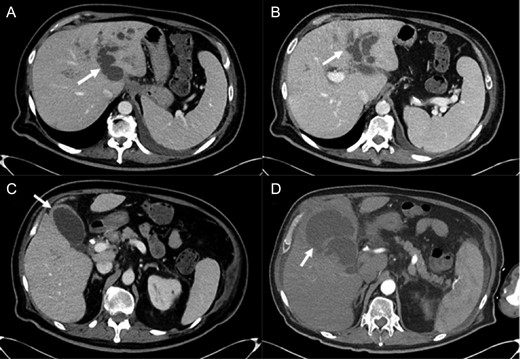

Abdominal imaging findings: axial computed tomography (CT) scan showing the intrahepatic dilation of the left sided biliary system (arrow) from cranial (A) to caudal (B), diffusely thickened gallbladder wall (C, arrow) and left intrahepatic abscess (D, arrow).

Repeat CT imaging revealed continued thrombosis of the left portal vein and anterior branches of the right portal vein and right hepatic artery (Fig. 3). Due to persistent left intrahepatic abscess and concern for an underlying obstructive process in the left biliary system, the patient underwent an endoscopic retrograde cholangiopancreatography (ERCP) which revealed choledocholithiasis which was removed followed by sphincterotomy and stent placement. He subsequently underwent a spyglass™ procedure which noted a left biliary tract occlusion secondary to a mass which was biopsied. Pathology, however, was noted to be benign with debris and bile crystalline material and rare fragments of fibrous tissue with biliary-type epithelium.